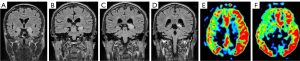

Antibody-mediated AE can be divided into two categories based on lesion location: diffuse encephalitis, which includes anti-NMDAR encephalitis and MOG antibody cortical encephalitis, and limbic encephalitis, which includes anti-LGI1 encephalitis, anti-Caspr2 encephalitis, anti-GABABR encephalitis and anti-GAD65 encephalitis. Figure 1 shows the lesion probability map for all subtypes of AE (Figure 1A) and for different antibody-mediated AE (Figure 1B).

In this study, MRI abnormalities were lower than that of EEG (62.2% vs. 95.6%, P<0.05). Imaging typically showed common features across different antibodies, manifesting as T1 hypointensity, T2 FLAIR hyperintensity or mild hyperintensity, and normal or mild hyperintensity on DWI, which was consistent with previous studies (14,19,20). We also produced lesion probability map for all and different subtypes of AE, which showed that medial temporal lobe and hippocampus were the most affected locations across all subtypes of AE, while different subtypes of AE involved different locations.